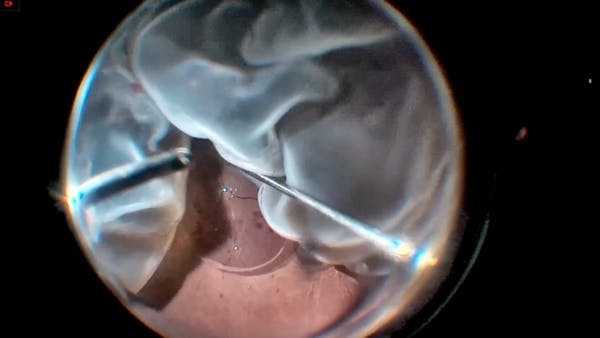

Dense Preretinal Membranes

Alan J. Franklin, MD, PhD